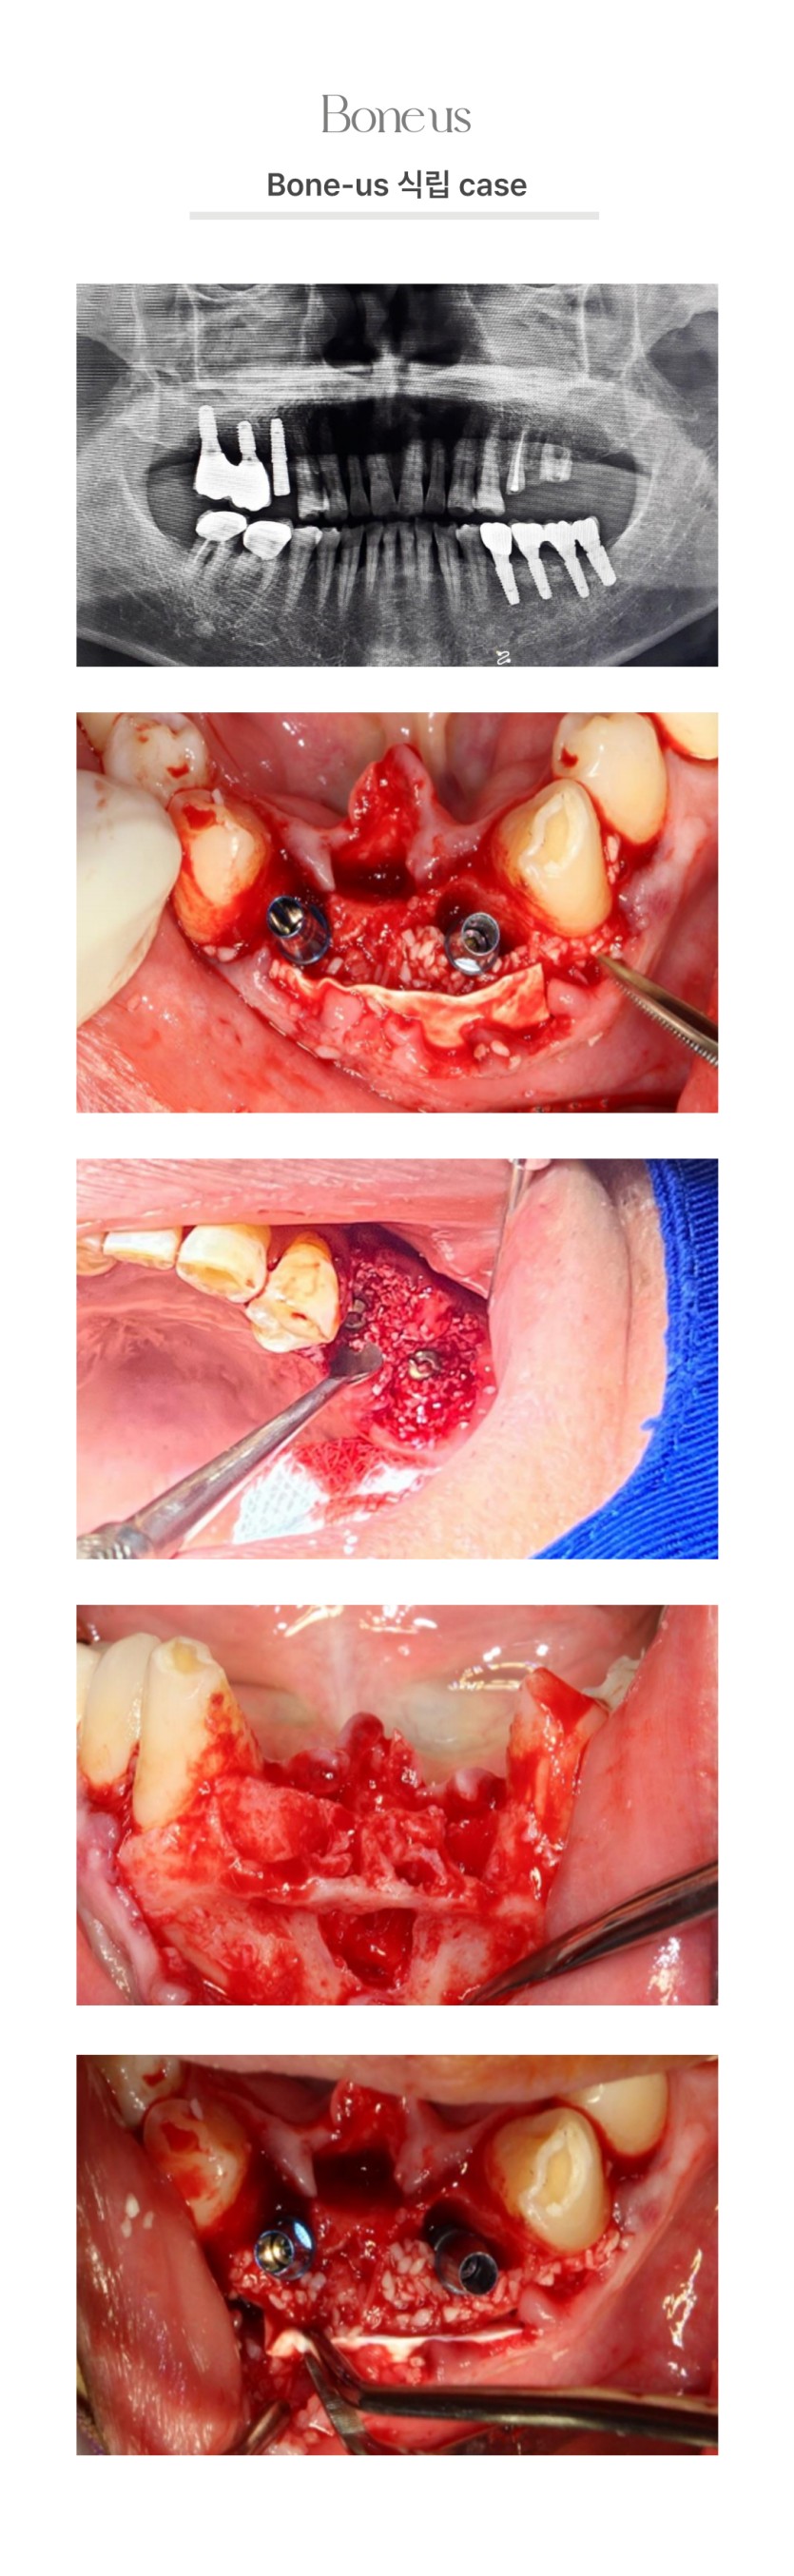

CLINICAL CASE

본어스 시술사례

본어스 식립 케이스 1